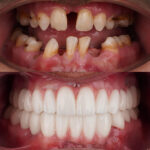

The All-on-4 “Before and After” journey is about more than just a dental procedure it is a total facial rejuvenation.

The most striking change in our patients isn’t just the new set of white teeth. The All-on-4 technique provides a “mini-facelift” effect.

Lip Support: When teeth are missing, the lips collapse inward. Our custom-designed All-on-4 bridges restore the natural volume of your lips.

Reduced Wrinkles: By restoring the correct height between your upper and lower jaw, we reduce the “sunken” look around the mouth and chin.

The “Before” Stage

Most of our patients come to us with:

Advanced gum disease or failing bridges.

Loose, uncomfortable removable dentures.

Difficulty eating anything other than soft foods.

The habit of covering their mouth when laughing.

The “After” Stage (The Final Masterpiece)

After 3 to 4 months of healing, the permanent bridge is fitted. Our “After” photos showcase:

Perfectly aligned “Hollywood” or “Natural-Look” smiles.